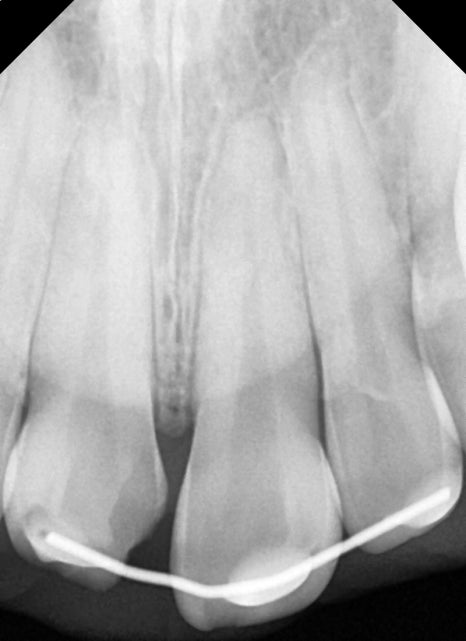

첫 번째 환자분과 다르게 이분은 치아의 동요도도 관찰되었기 때문에 사진처럼 치아를 고정할 수 있는 임시 치간 고정술을 진행했습니다.

흔들리는 치아는 정도에 따라 고정 장치의 유지 기간이 좀 다를 수 있지만 일반적으로 2~4주 이상은 권하고 있지 않습니다.

엑스레이 내에서 추가적인 치아 파절의 흔적은 보이지 않아 치아의 흔들림을 고정시킨 후 치아 파절 부위나 치아 신경의 생활력을 평가하기 위해 2주 후 체크를 해봤습니다.